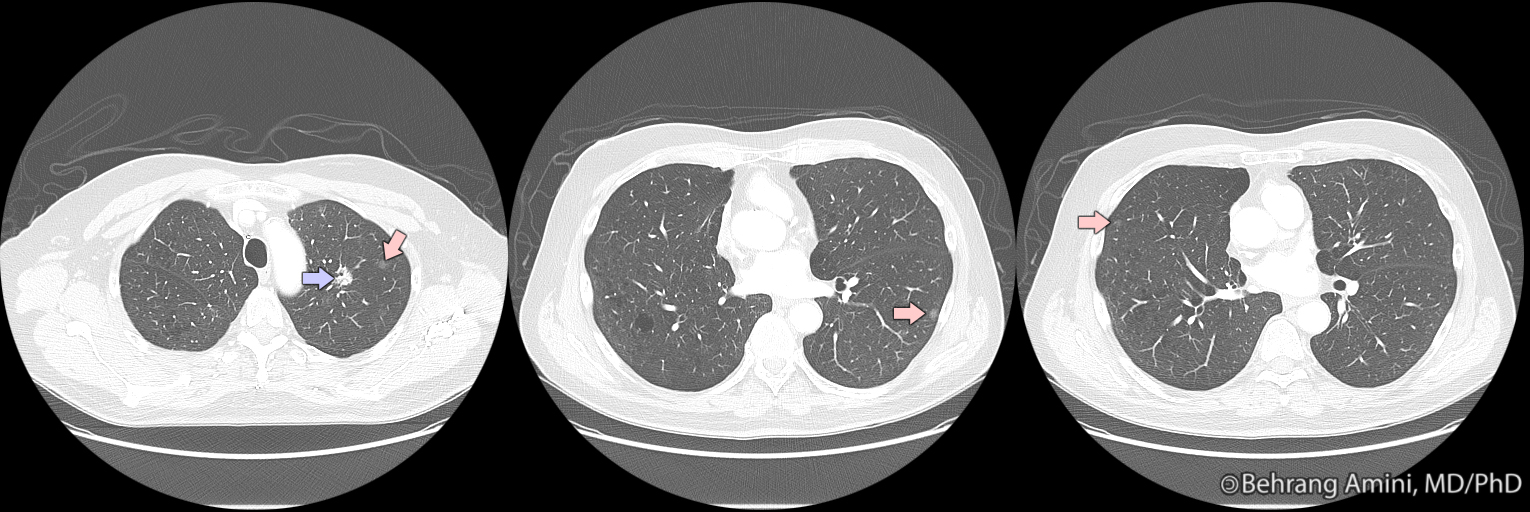

Ground glass opacity, focal (A) and confluent (B) form. Download